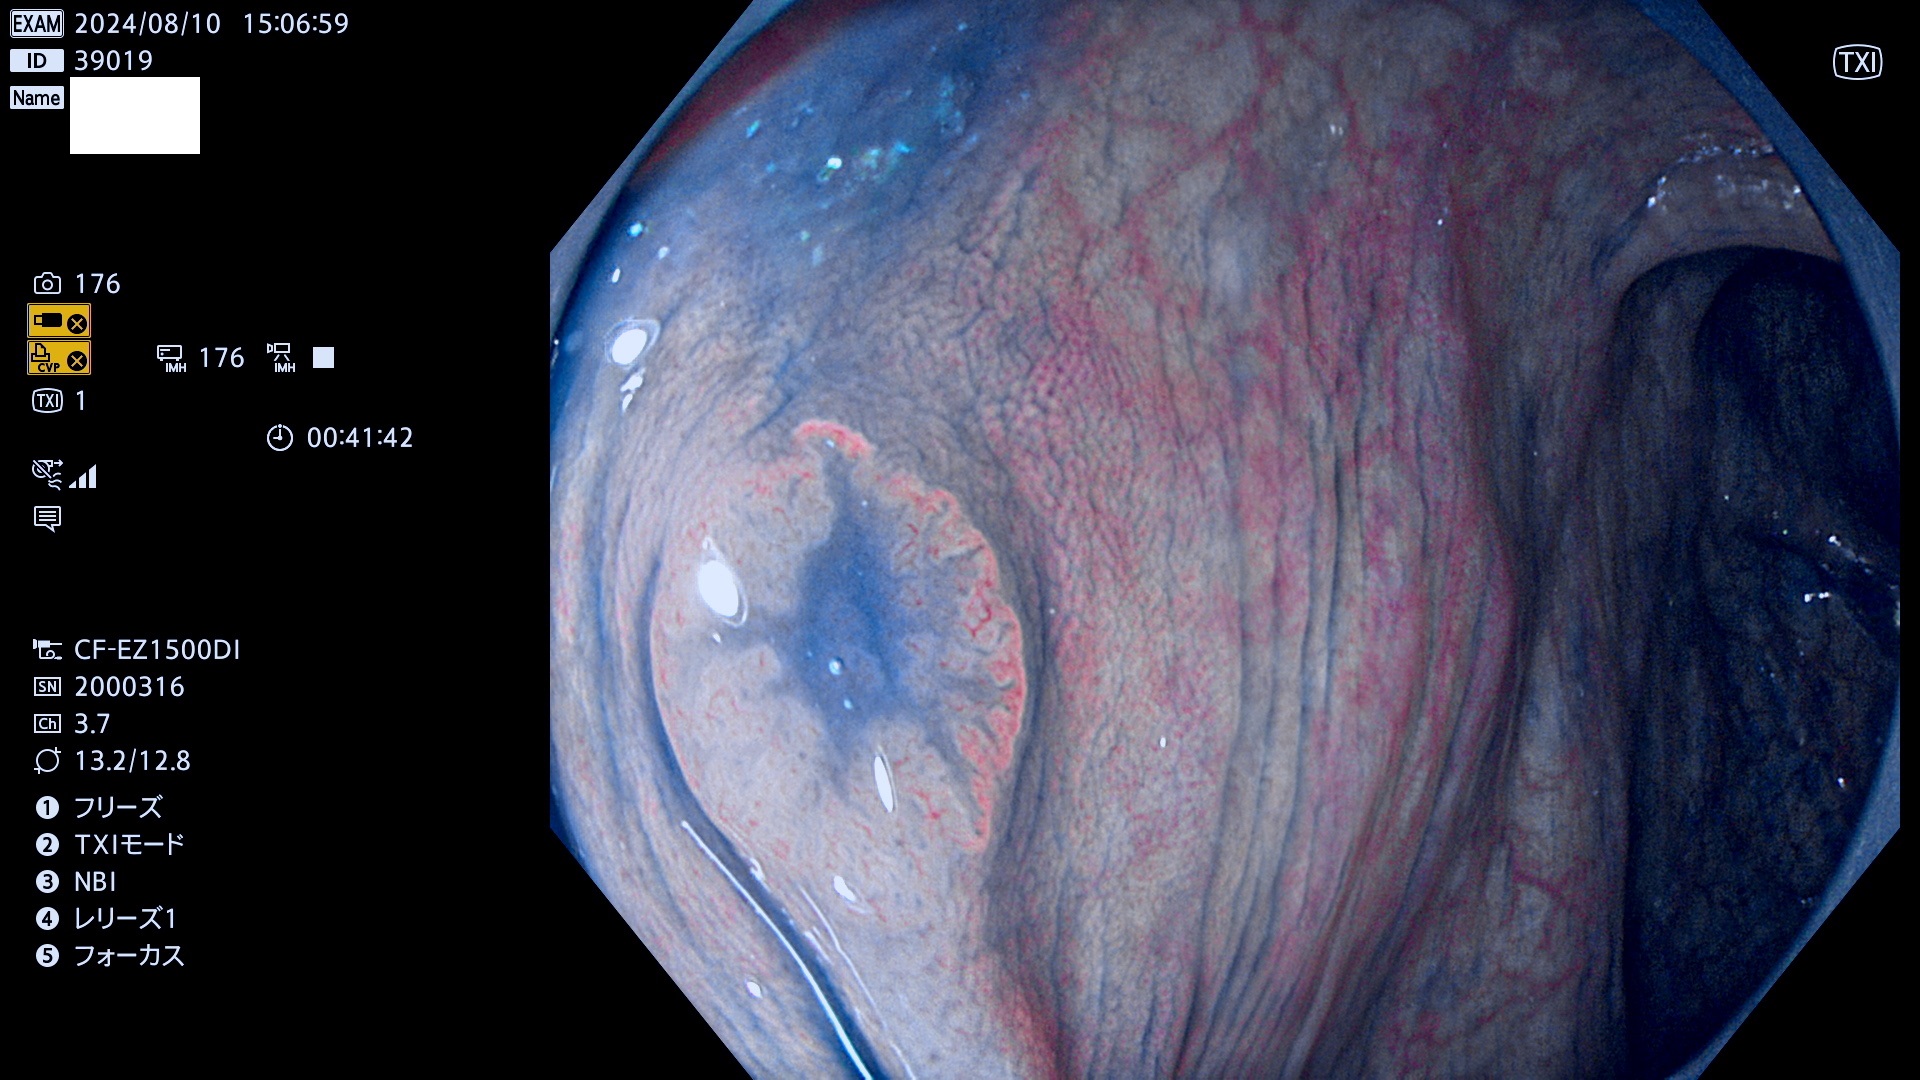

今週のUb、Uc型腺腫

完全に平坦な物をUb、陥凹している物をUcと呼びます。最も発見が難しく危険な病変です。

毎週の検査(木・金・土・日)に発見されたUb、Uc型・腺腫を、その週の日曜の夜にUPし1週間、提示します。

抽出の対象期間 2024年8月8日〜8月11の4日間(30件の検査)11件 (11/30=35%)